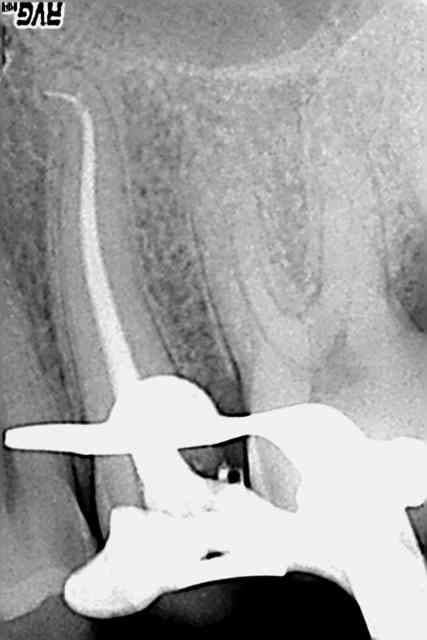

Bon je sais pas comment vous faites. J'ai fait ça ce matin, au protaper, sans mettre très longtemps, sur le contre angle endo, sans rien de spécial dans ma séquence. Et je casse pas. Et j'ai pas de déplacement de canal. Bref je suis entièrement satisfait des protapers.

Edit : 2eme radio sans l'apex, la dent est très longue j'ai eu du mal à viser (26mm). Obturation mixte : fouloir + thermomécanique au mac spadden.

Concernant la première, est ce que ton dernier instrument a été jusqu'à l'apex, ou bien s'est il arrêté juste avant la courbure finale (très serrée).Et ce que l'on observe à la radio serai simplement la fusée de l'obturation qui suivrai le cathétérisme ?

C'est en aucun qu'un une critique ou un jugement simplement une question que je me pose vraiment.

Je me le demande aussi, je suis presque sur d'avoir cathétérisé à 0,5mm de l'apex (localisateur + digue) et par la suite j'ai amené tous mes instruments à cette LT (simplement S1, S2, F1, F2, pas de SX/endoflare, pas d'US pas de gates). Bon j'ai jeté les instruments après usage :).

Par contre pas de radio entre préop et obturation, la patiente avait juste RDV pour une "douleur au froid". On comprend pourquoi.

Maintenant le gutta condensor 35/10ème sur 20 mm ça pousse fort en effet...peut être que les instruments n'ont pas vraiment pénétré le crochet. C'est peut être aussi la limite de la zone "tassée" qu'on voit, les fouloirs et condensors sont droits contrairement aux protapers.

J'ai eu la surprise sur la radio finale, je n'avais pas vu ce crochet sur la préop.

et par contre c'est la même 25, qui a bien 2 canaux (radios + ou - angulées)